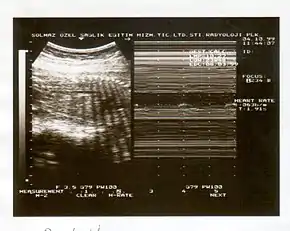

A biophysical profile (BPP) is a prenatal ultrasound evaluation of fetal well-being involving a scoring system,[1] with the score being termed Manning's score.[2] It is often done when a non-stress test (NST) is non reactive, or for other obstetrical indications.